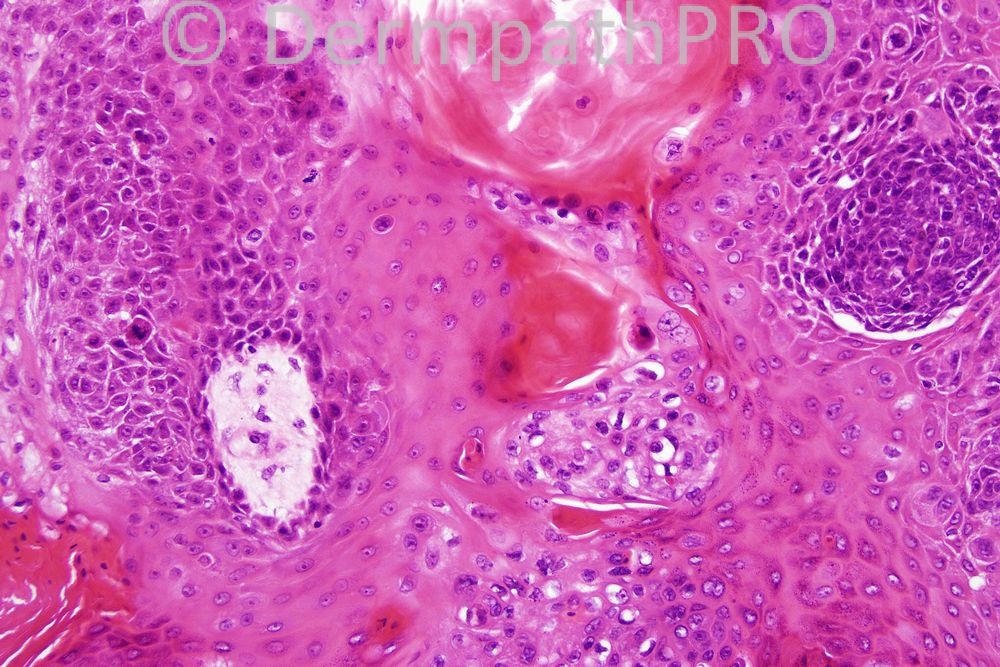

Male 60 years, scaly plaque on leg.

The final diagnosis was In-situ porocarcinoma. The differential diagnosis is listed below. Have a good weekend.